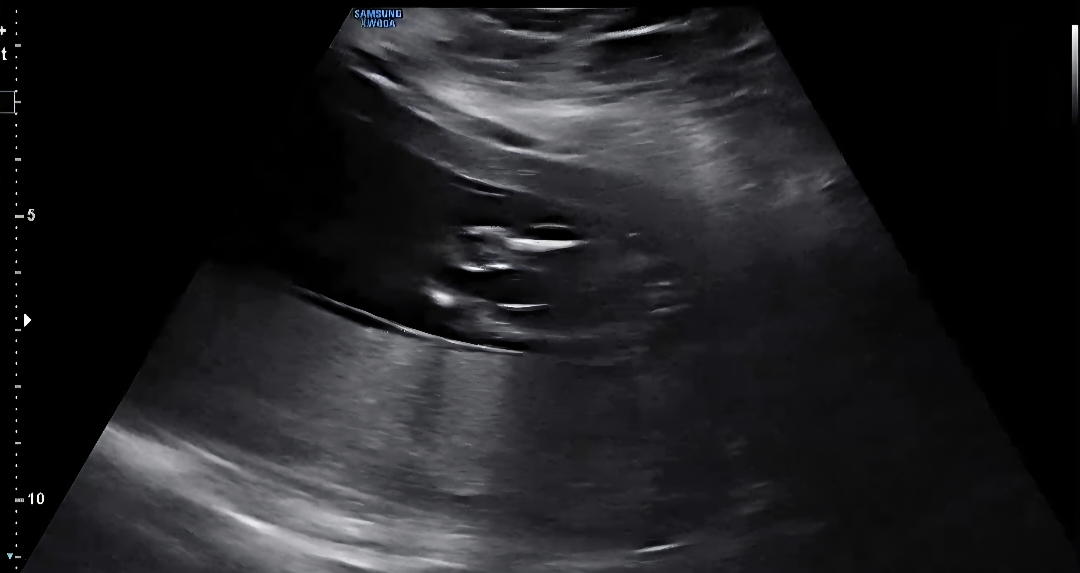

15주1일 다리사이.. 반전있을까요 ?

의사선생님은 95% 공주라하셨능데 혹시 반전 있을까욥 ..